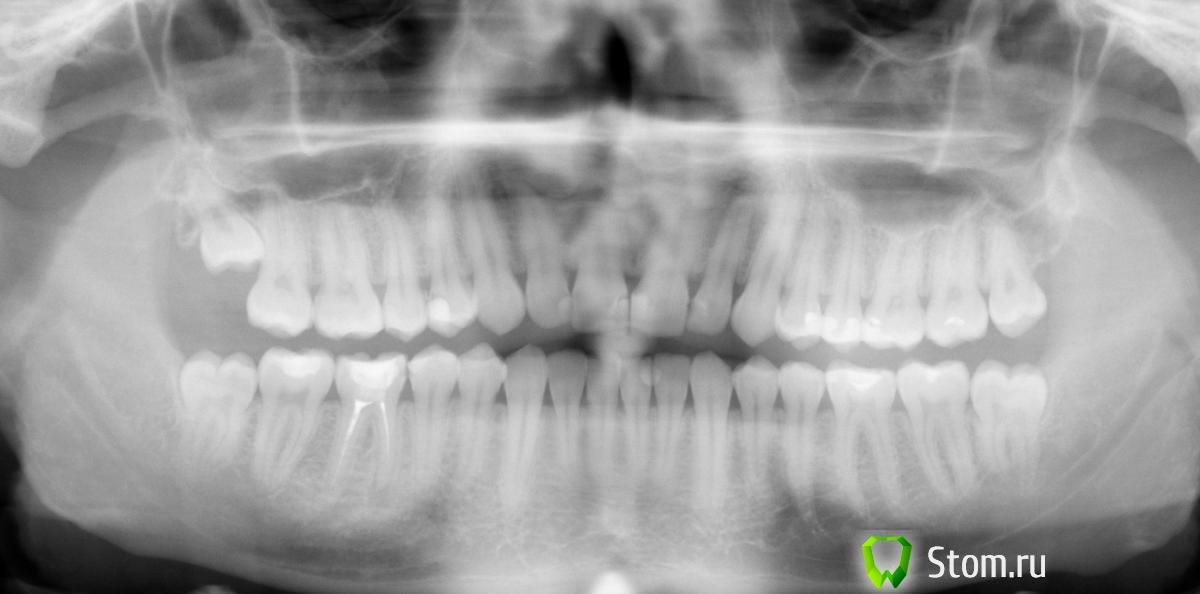

Pekarnik Опубликовано 23 января, 2012 Поделиться Опубликовано 23 января, 2012 Здравствуйте. Мужчина. 26 лет. Москва. Заранее извиняюсь за кривые объяснения и большое количество текста с грамматическими ошибками. -В 2004 году Доктор А удалил нервы, почистили каналы, делал снимки и запломбировали 46 зуб в платном стоматологическом отделении одной Гос Клиники. -В 2005 году показался тому же Доктору А, т.к. иногда возникали неприятные ощущения в области 46-ки. Доктор А после осмотра (не помню дедали ли снимок)сказал, что вероятнее всего это просто повышенная чувствительность в соседнем 45-ом зубе и предложил пока ничего не трогать и понаблюдать.-Всё нормализовалось. Прошло несколько лет.- В 2009 году сделали СНИМОК-1. Обнаружили гранулему на данном зубе, но я ничего стать делать - осел.В общем только сейчас добрался до доктора. Тот же Доктор А. Сделали Снимок-2.- Доктор А теперь говорит, что лечить гранулему в данном случае нецелесообразно ввиду плохого состояния зуба (большая пломба на 2 стенках, ослабленный зуб и корень) и что в процессе лечения гранулемы и каналов - есть большая вероятность что зуб, вернее корень сломается. Доктор А предлагает не лечить сейчас каналы и гранулему, а пока просто понаблюдать, делая снимок раз в пол года и настраиваться, что потом сразу удаление и имплант. Говорит, что гранулема не очень большая и что если нет жалоб - то можно не спешить, что она ещё может и 5 и 7 лет быть в таком "сонном состоянии" состоянии.Учитывая вышесказанное лечить у Доктора А зуб на котором возникла гранулема после его же лечения я не стал. Сходил ещё к 2 докторам. -В одной маленькой частной клинике Доктор Б предлагают перелечить каналы за 15 000 + коронка от 15000. + говорят что возможно рассасывается не кость у верхушки корня, а возможно и сам корень!!! Это видно на снимке?-В одной средней сетевой клинике Доктор В предлагает не перелечивать зуб а поставить пломбу и наблюдать раз в пол года.Ещё стоит упомянуть, что у зуба появился красноватый оттенок, врач сказал что заделан резорцин-формалином скорее всего.---------------------------------------------------------------------------------------- Прикладываю два снимка 2009 и декабрь 2011 года.------------------------------------------------------------------------- вопросы:1. Что делать с зубом? Не трогать (советуют 2 доктора)и поставить пломбу, так как : а. Особо не беспокоит и вроде как не увеличивается с 2004 года. б. Есть вероятность что не смогут распломбировать формалин и пройти каналы. в. Только потревожат гранулему, усугубится ситуация. г. Лечение относительно дорогое. Перелечивать каналы. Долбить формалин и ставит коронку, так как: а. гранулема может вырасти значительно за несколько месяцев и не удастся её контролировать даже делая снимки раз в пол года. б. пломба скоро сломается, зуб разрушится дальше и будет сложно поставить потом коронку. 2. Если перелечивать, то насколько это сложно учитывая резорциновые каналы. Нужна ли специальная квалификация, опыт, микроскоп, или это стандартная процедура в настоящее время и любой среднестатистический терапевт это выполняет на ура? Смущает, что доктор В (стаж более 5 лет), который в целом меня устраивает - настойчиво рекомендует не ковырять зуб, а ставить пломбу. Может это быть обусловлено в том числе не желанием сложной работы или недостатком квалификации, неуверенность за результат? 3. Можно ли и стоит ли данный случай (возникновение гранулемы) считать некачественным лечением и просить провести бесплатное лечение в отделении доктора А, который лечил эти каналы? Большое спасибо! Ссылка на комментарий